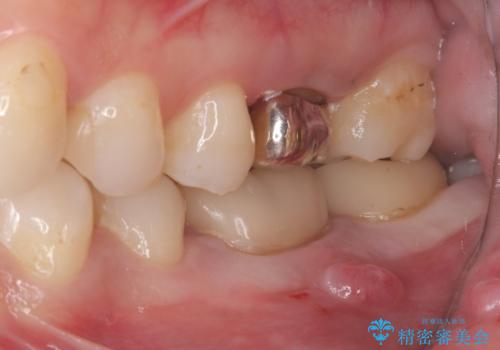

咬合力によるヒビの部分に生じる歪みを軽減するため、クラウンを被せました。

咬合力によるヒビの部分に生じる歪みを軽減するため、ヒビを追えるところまで切削しCR裏層・支台歯形成を行い、一度仮歯に置き換え症状の緩和を確認し、CAD/CAM冠を装着しました。